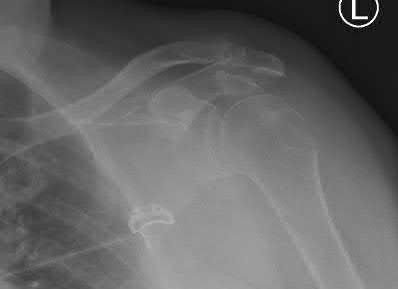

A 55-year-old patient presents with a slowly enlarging, painful mass in the proximal humerus.

Biopsy reveals a hyaline cartilage matrix with cellular atypia, confirming a diagnosis of central conventional chondrosarcoma. Which of the following genetic mutations is most frequently identified in this specific tumor?